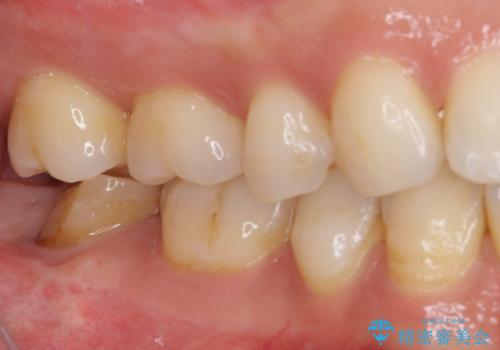

根管治療後の土台も構築されていたので、仮歯に置き換えた後にフルジルコニアクラウンにて補綴することとしました。

遠心の歯肉が盛り上がっていたため、清掃性が悪くなる懸念がありましたが、クラウン装着による歯肉の腫れは認められませんでした。